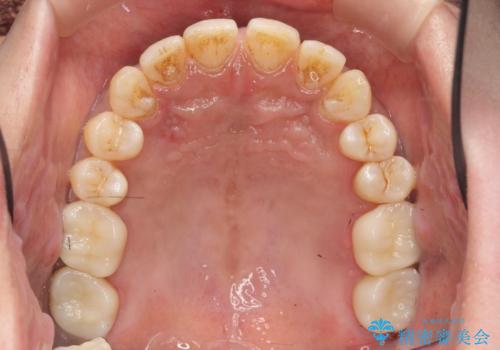

歯槽堤保存術を併用したブリッジ治療

抜歯時に可及的に歯肉のボリュームを保つよう骨充填材とコラーゲン製剤による填塞を行い審美的かつ機能的なブリッジとなるよう治療を進めます。

- 66万円(ジルコニアクラウン×5・仮歯×5)費用は治療当時の料金となります

一件綺麗に見えるセラミックも適合や精度が悪いと、内部で虫歯が進行し亀裂や破折、悪臭の原因となることがあります。